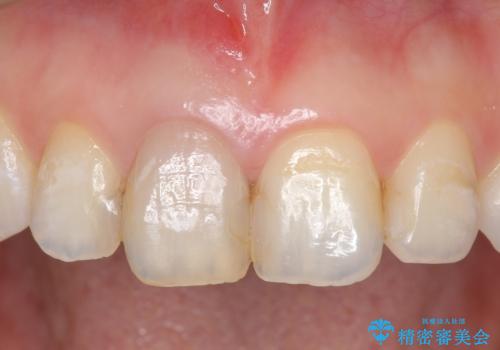

- 右上1番目の歯の変色が気になると来院された方の症例です。

検査の結果、右上1の歯は失活(歯の神経が死んでいること)していたため根管治療を行いました。

その後オールセラミッククラウン(スペシャル)による補綴を行いました。

なお隣在歯の樹脂は今後治療していく予定です。